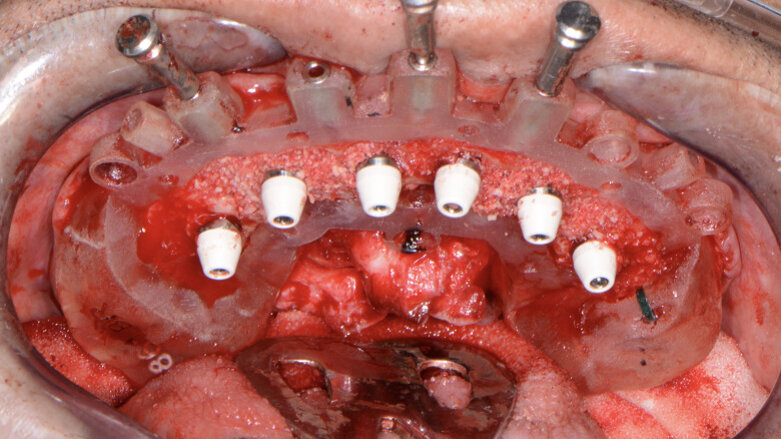

Fig. 13: Implants with corresponding multi-unit abutments.

A baseline Implant Stability Quotient reading was taken of these implants utilising the Penguin RFA unit (Aseptico). Since the initial readings were all above 70 and the quality of bone after levelling was good, multi-unit abutments (OCO Biomedical) were tightened into the Engage dental implants at 25 Ncm, followed by temporary cylinders at 15 Ncm. Any residual areas around the implants or in the sockets were grafted with a cortical mineralised and demineralised bone grafting material to optimise the area for regeneration (Fig. 13).